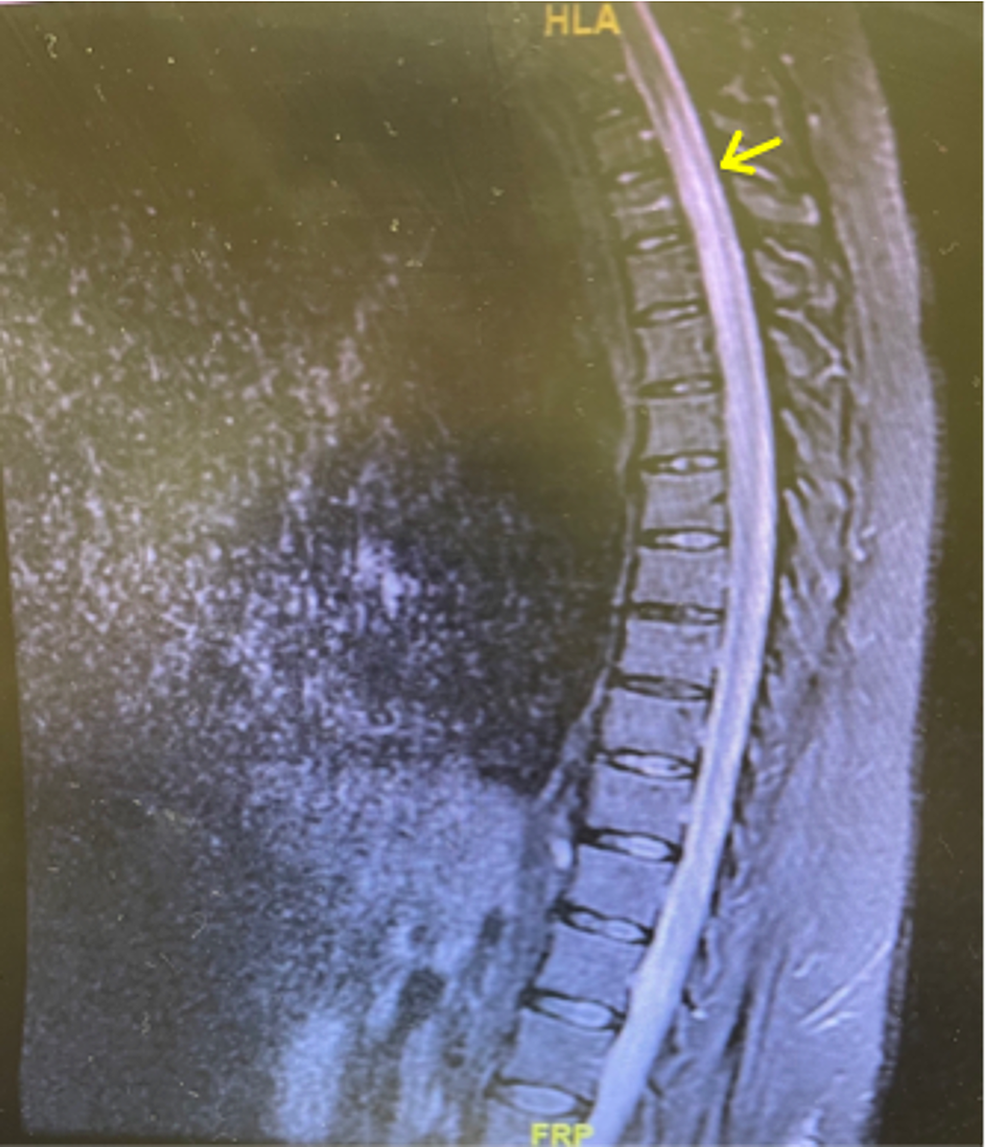

Figure 1 from A Rare Case of Tabes Dorsalis Semantic Scholar Tabes Dorsalis Article Tabes dorsalis is the result of an untreated syphilis infection. Tabes dorsalis is much more common in men than women, and. Tabes dorsalis, a potential but now rare manifestation of tertiary syphilis, is an example of a degenerative disease that affects the dcml pathway and results in severe neurological deficits. The credit for the first clinical and pathological description of. Tabes Dorsalis Article.

Tabes dorsalis Image Tabes Dorsalis Article Tabes dorsalis is much more common in men than women, and. Tabes dorsalis is the neurological manifestation of a previous infection with. Tabes dorsalis is the result of an untreated syphilis infection. The credit for the first clinical and pathological description of tabes dorsalis is attributed to moritz heinrich romberg 1) who, in 1840,. Tabes dorsalis, also known as locomotor. Tabes Dorsalis Article.